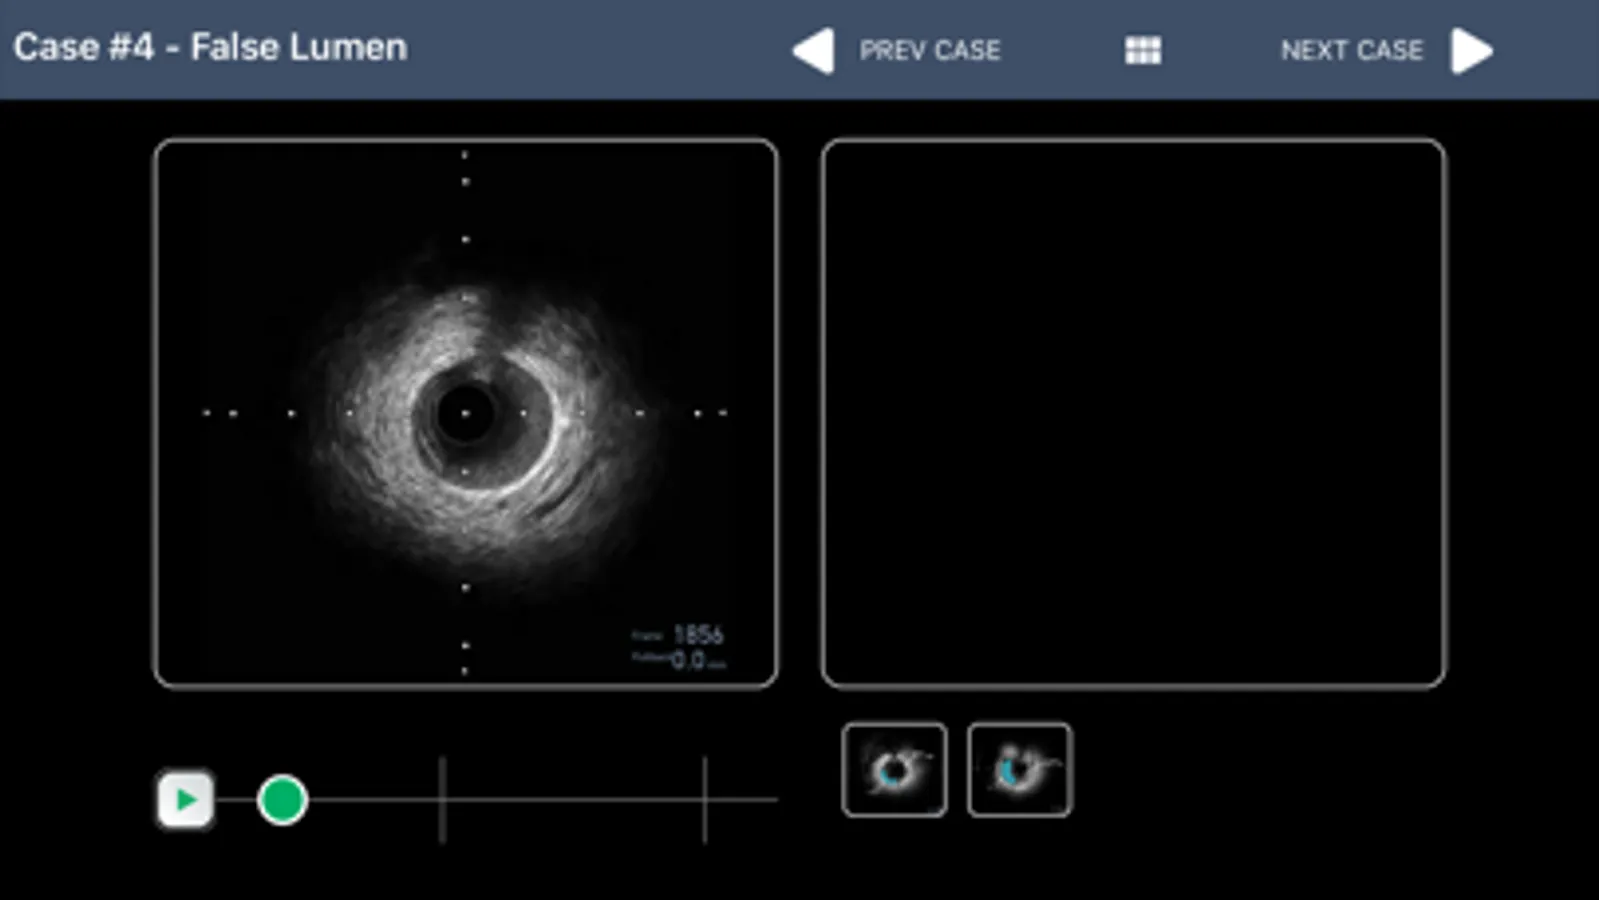

• IVUS image and FFR waveform interpretation guide with questions

• IVUS video clips with image interpretation guide